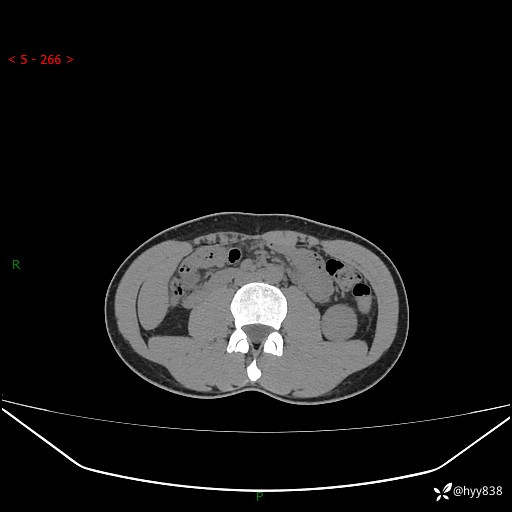

现病史:患者昨日中午进食后出现明显腹痛,腹泻,在我院急诊科行补液及对症治疗,双肾输尿管彩超提示左肾占位(5.2*4.3cm),平素无明显腰痛,无再发肉眼血尿等情况,现为求处理左肾占位,遂来我院,门诊以左肾占位收治入院。 患者起病以来,精神、食欲、睡眠尚可,大便可,小便如上,体力体重无明显下降。

双肾CT平扫+增强(三期)